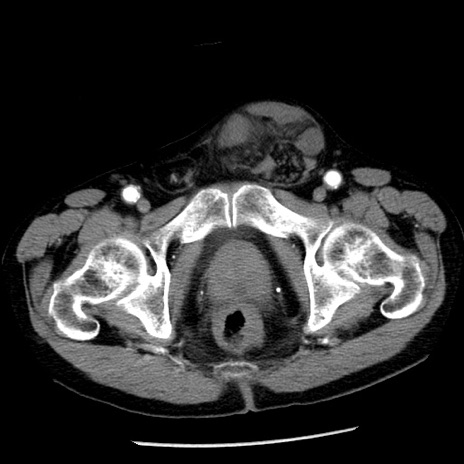

冠状断像

【症例】80歳代男性

【主訴】嘔吐

【現病歴】昨晩2回嘔吐あり、今朝になっても嘔吐あり。来院。

【既往歴】胃潰瘍

【身体所見】意識清明、BT 37.6℃、BP 166/95mmHg、HR 100bpm、SpO2 97%、腹部:平坦・軟、腸蠕動音聴取良好、圧痛なし。

【データ】WBC 21900、CRP 1.46